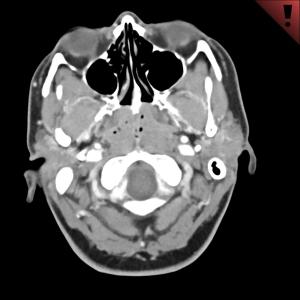

Can you properly diagnose this 30-year-old female?